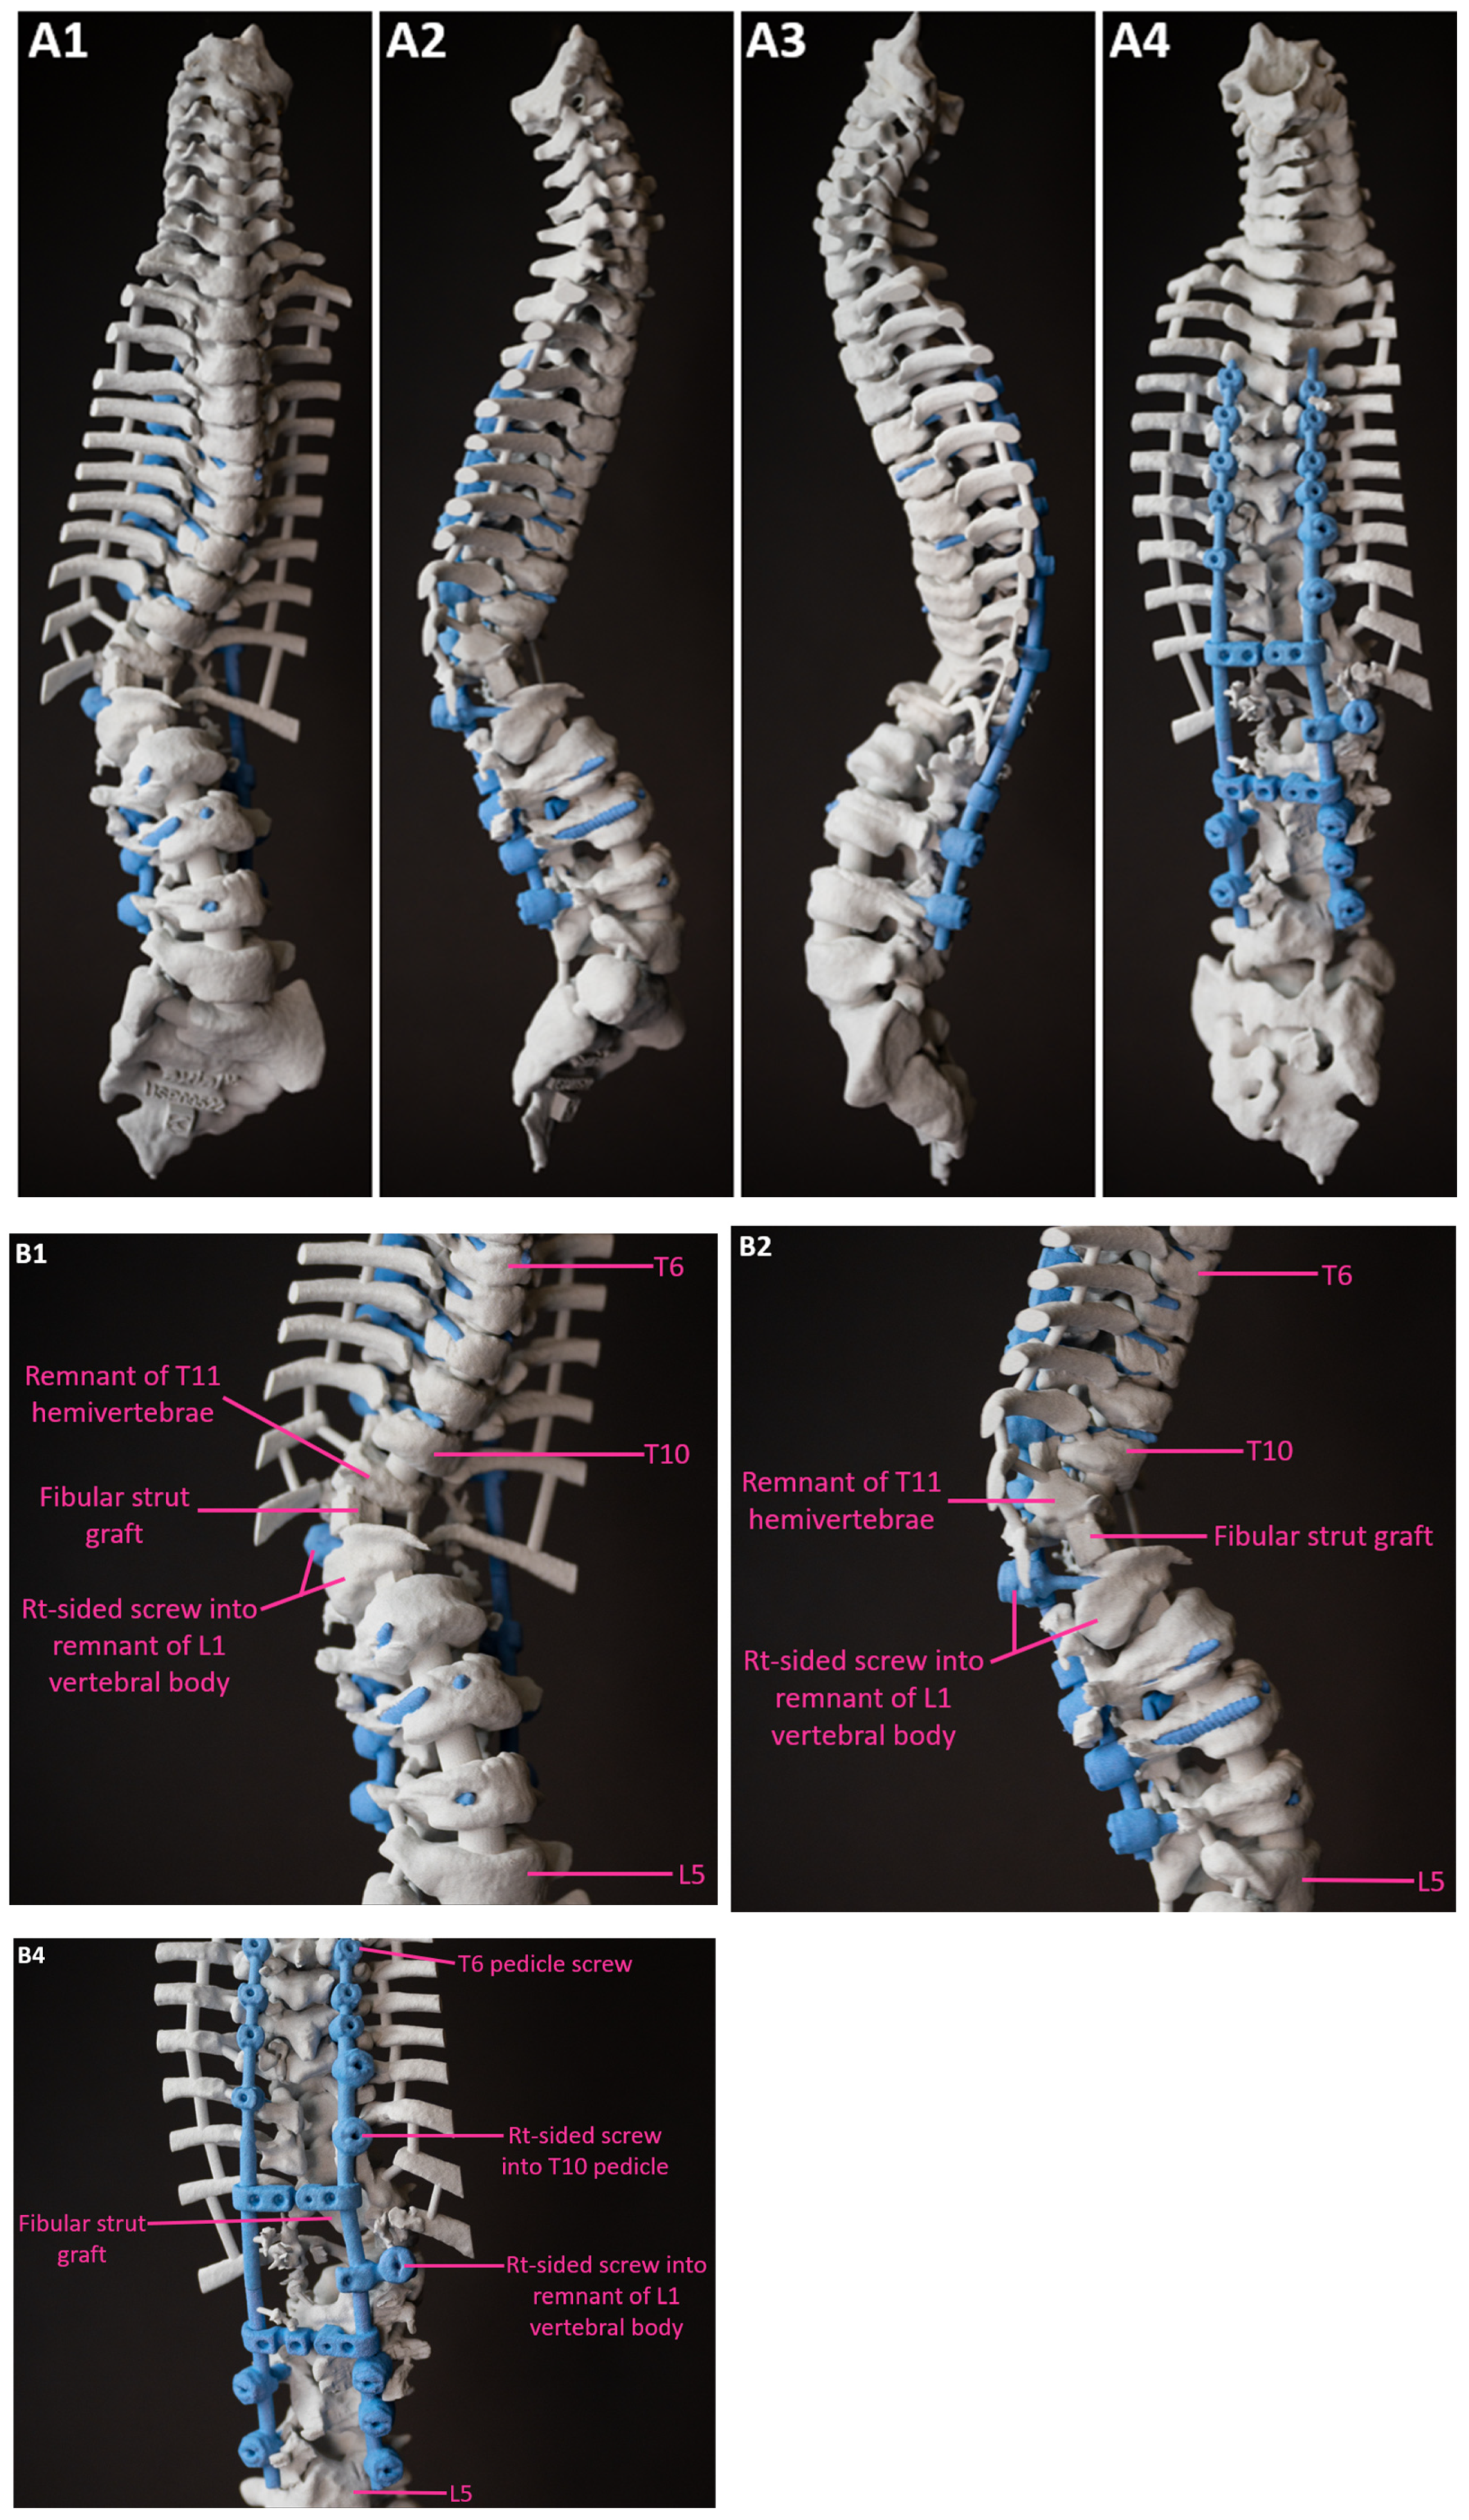

Figure 11.

Full length (A) & partial (thoracolumbar) (B) images of the post-operative 3D spine biomodel. 1—Anterior, 2—Right lateral, 3—Left lateral, and 4—Posterior views. T—Thoracic; L—Lumbar.

Figure 12.

Postoperative CT scan images verified bone formation across the congenital defect, and clinically, he was balanced in both sagittal and coronal planes (Figure 9, Figure 10, Figure 11 and Figure 12).